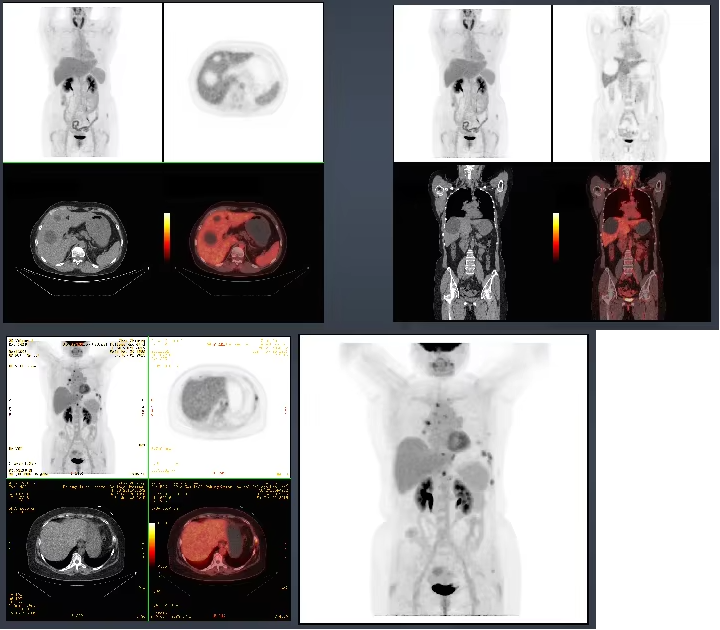

PET-CT integrates PET and CT. PET provides detailed molecular information such as function and metabolism of the lesion, while CT provides accurate anatomical location of the lesion. A single imaging can obtain sectional images of all directions of the body, which is sensitive, accurate, specific and accurate in positioning. It can clearly understand the overall condition of the body at a glance, and achieve the purpose of early detection of the lesion and diagnosis of the disease. The emergence of PET-CT is another revolution in medical imaging, which has been recognized and widely concerned by the medical community, and can be called the “crown of modern medical science and technology”.

PET-CT is the integration of the functions of the most advanced PET scanner and advanced spiral CT equipment. It is mainly used in the early detection and diagnosis of major diseases in the fields of tumor, brain and heart.